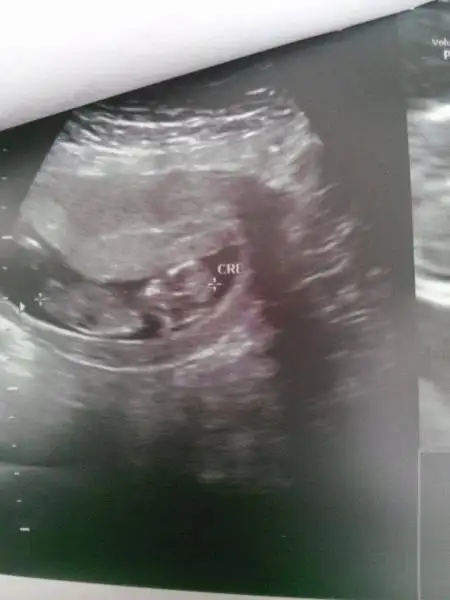

kızlar mrb bende 10+4 teki usg fotosunu koyuyorum yorumlarsanız çook sevinirimm

ne olursa olsun hepimizin sağlıklı olsun :)

nub belli değil ama anlaşılmıyor. acaba kız mı?

canım cevabin için teşekkür ederim. Sanki bacaklarini havaya kaldirmis poposu net görünüyor pozisyonu müsait aslında cikinti olsa görünmez miydi bilemiyorum ki ama cikinti bende göremiyorum kiz olabilir mi diyorsun yani canim doktora gitmeme 3 hafta var daha

bizim seninle aramızda 1 gün var. iki gün önceki ultrason görüntüsünü koydum. hala bişey diyen olmadı. ama benimkinde de çıkıntı net değil. bende tam anlayamadım. kız mı dedim kendi kendime. ama 1 oğlum var bu da kız olsun isterim yani, o yüzden mi kıza yoruyorum bilmiyorum. ama erkek nubu popoya paralel değil dik se eğer kız olma ihtimali daha yüksek bence. paralel net anlaşılmayabilir ama erkek anlaşılır bence, bu nub yöntemi aksi çıkan varmı bilmiyorumki